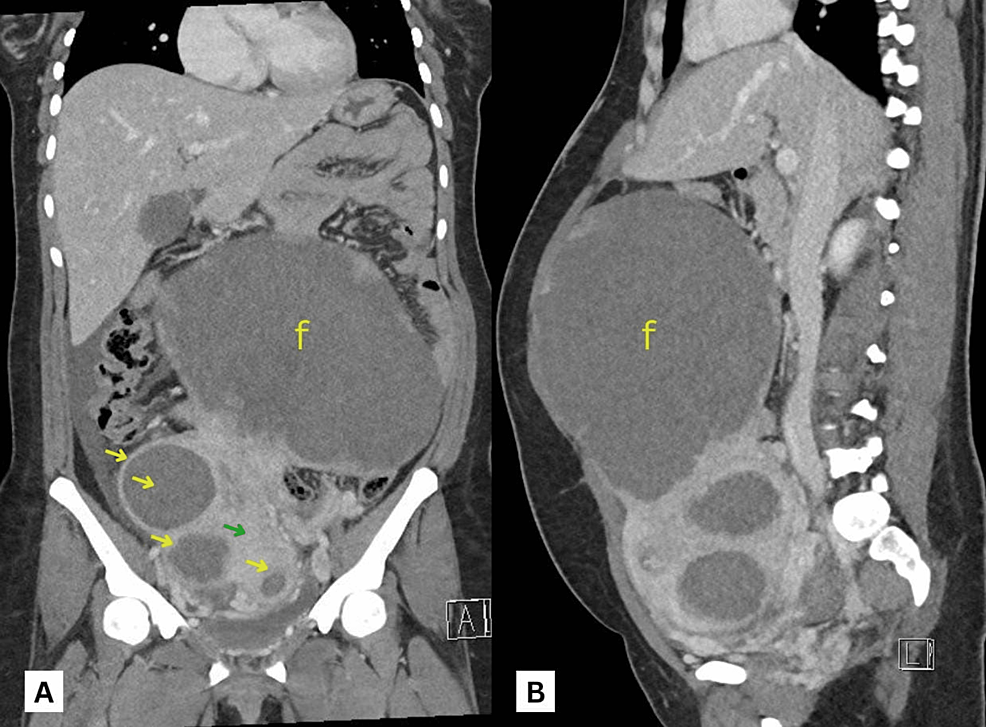

Small Bowel Obstruction as a Complication of Uterine Fibroids: A Case Report

Source : https://www.cureus.com/articles/145619-small-bowel-obstruction-as-a-complication-of-uterine-fibroids-a-case-report

Uterine fibroids are a common, benign gynecological smooth muscle neoplasm highly prevalent in women of reproductive age which can lead to multiple complications including small bowel obstruction. We report a...

Conclusion: Despite bowel obstruction being a rare complication of uterine fibroids, it can be fatal if not promptly diagnosed and managed early, causing considerable morbidity and mortality. Diagnosis of this complication becomes even more challenging if the concerned fibroid(s) is large enough to occupy the abdominal cavity and displace the...